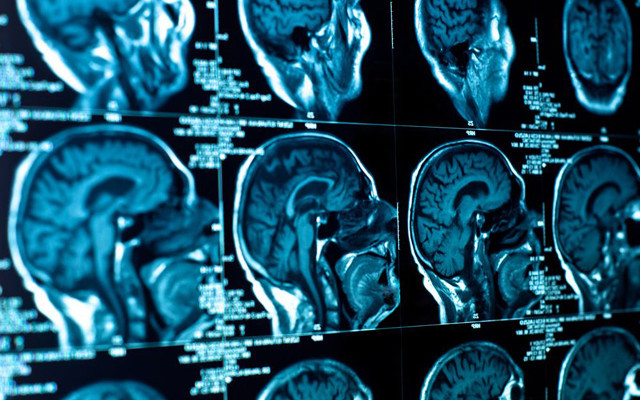

»Chemo-Brain« – Dauerhafte Schädigung des Gehirns durch Chemotherapie

Teile die Wahrheit! Dass das »Chemo-Brain« – Chemo-Gehirn – real ist, wird von Wissenschaftlern bestätigt. Sie fanden klare Beweise dafür, dass die kognitiven Fähigkeiten von Patienten, die eine Chemotherapie durchmachen, beeinträchtigt sind. Wie die neuen Studien zeigen, kann eine Chemotherapie zu Konzentrations- und Erinnerungsstörungen führen, die sich in einer Art »Gehirnnebel« äußern, wie viele Teilnehmer … »Chemo-Brain« – Dauerhafte Schädigung des Gehirns durch Chemotherapie weiterlesen